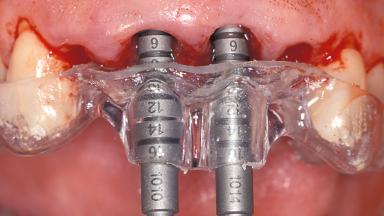

Replacement of the Four Maxillary Incisors with a Fixed Dental Prosthesis Using an Immediate Loading Protocol

In November 2001, a 53-year-old female presented seeking advice and options for treatment of her maxillary incisor teeth. She was dissatisfied with both the functional and esthetic qualities of her existing restorations. Her medical health was excellent, and she reported no contraindications to dental care. On presentation, the patient’s dental health was less than ideal. Although she had no probing depths greater than 3 mm, she suffered from generalized chronic adult periodontitis and displayed multiple sites of bleeding on probing. Her remaining dentition was heavily restored, and many teeth had been endodontically treated. Areas of recurrent dental caries were noted on many teeth. Radiographically and clinically, the maxillary incisor teeth exhibited large areas of active caries, and after the splinted crowns had been removed, the teeth were determined to be non-restorable.

Placement Protocol Immediate implant placement

Tooth Site Maxillary incisor or canine

Loading Protocol Immediate